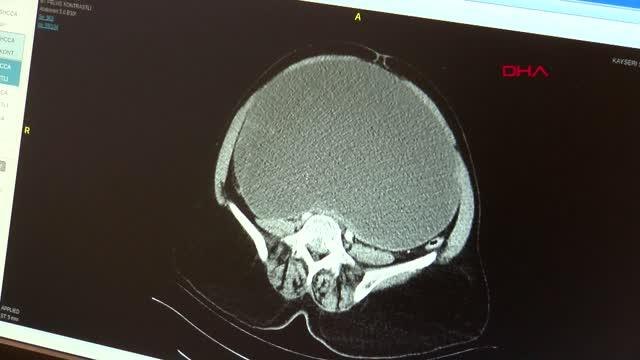

İzmir'de bir hastanede sağlık memuru olarak görev yapan Seden Baş, göğsündeki şişliği kedi tırmığından kaynaklandığını düşünerek doktora başvurdu. Yapılan tetkikler sonucunda Baş'ın meme kanseri olduğu ortaya çıktı.